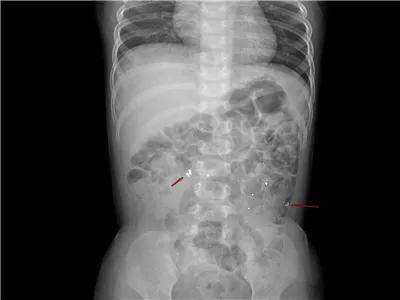

6岁·磁力珠

5小时前不慎误服磁力珠,未见呕吐,无腹痛。

2岁·磁力珠

1天余前误吞磁力珠9颗,每颗直径2mm左右,误服时孩子主诉食管部位不适。

单个磁铁的危险性不大,但是多个磁铁进入体内后,在不同的消化道会紧紧地吸在一起,强烈的吸力会导致消化道穿孔。